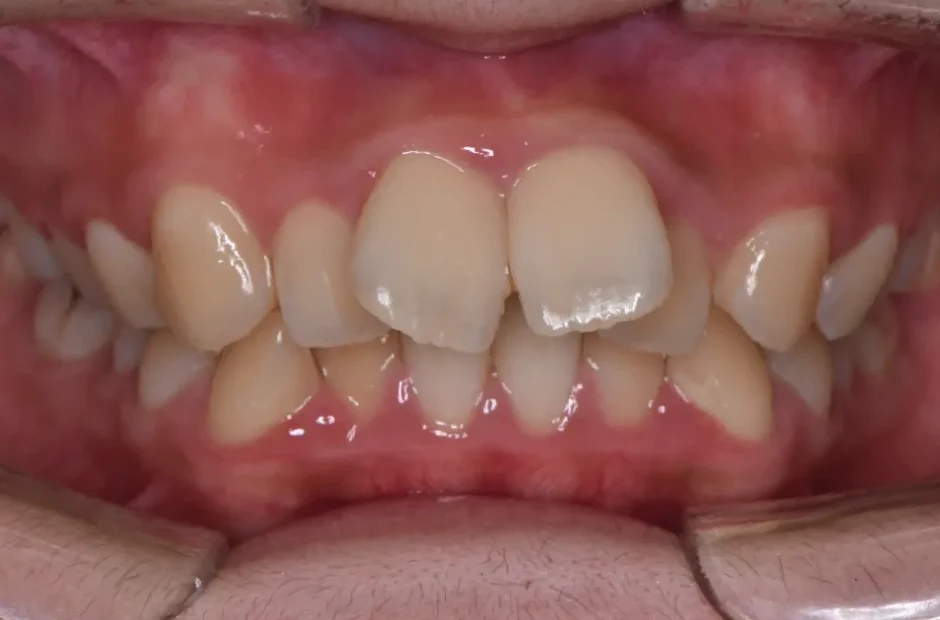

叢生

| 診断名・主訴 | 叢生 |

|---|---|

| 年齢・性別 | 43歳・女性 |

| 治療期間・回数 | 2年7か月 27回 |

| 治療に用いた主な装置 | 舌側矯正 |

| 抜歯部位 | 両顎4,4 |

| 治療費 | 100万円(税抜) |

| リスク・副作用 | 装置による違和感・疼痛・歯肉退縮・歯根吸収・虫歯のリスクなど |

治療前

治療中

治療後